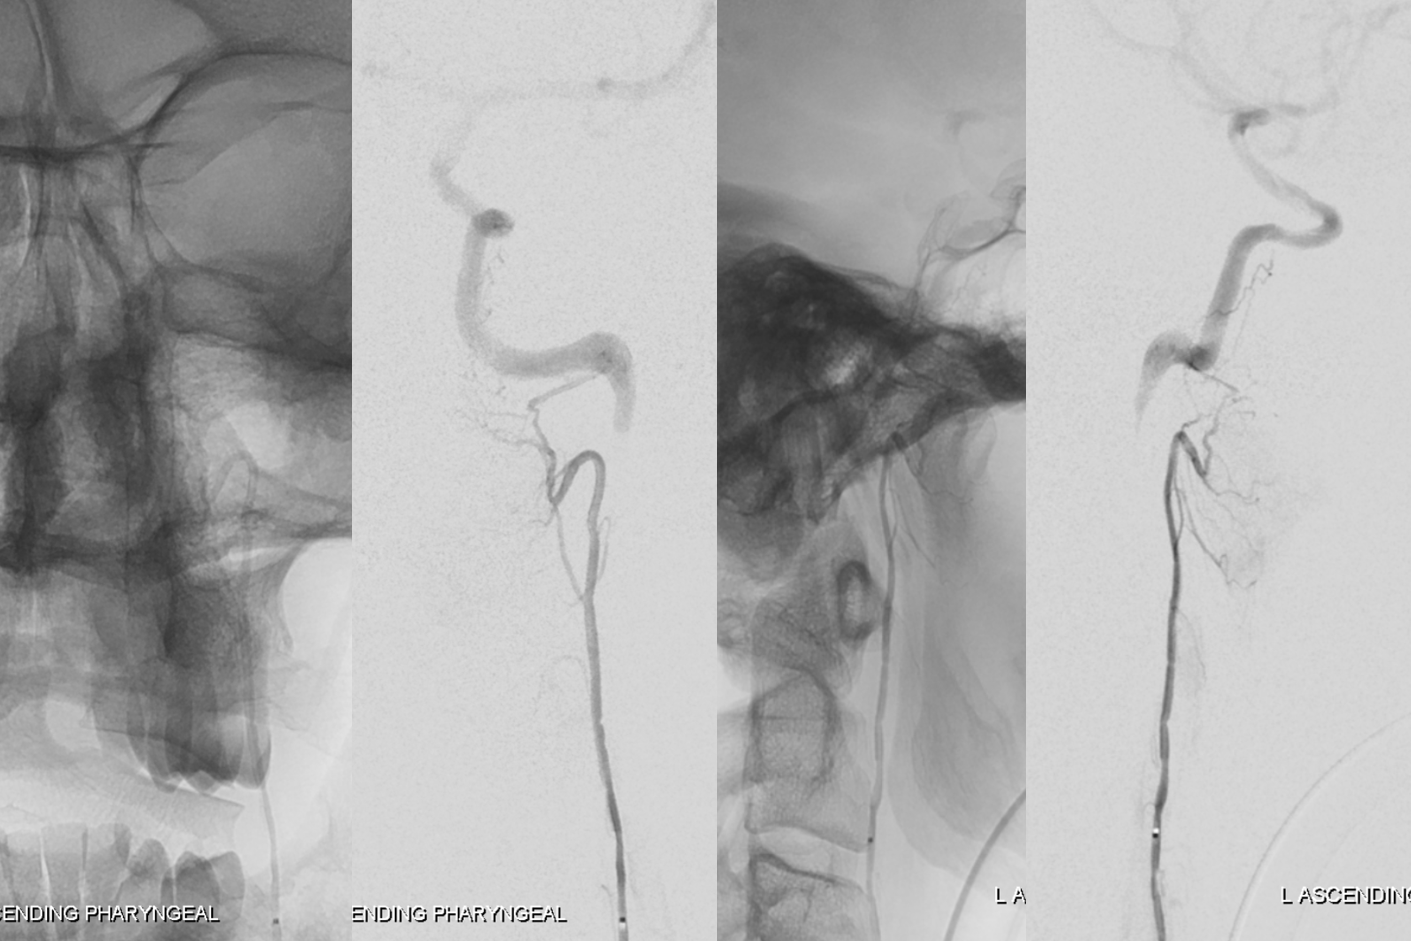

Sigmoid sinus fistula, neuromeningeal trunk:

Another demonstration of sigmoid branch supply to a sigmoid sinus fistula, also being fed by occipital and lateral tentorial (MHT) branches. Notice also musculoskeletal branch contribution to the fistula which on the lateral may be mistaken for an odontoid arch branch.

Red=neuromeningeal trunk and jugular division thereof; white=sigmoid branch; yellow=hypoglossal division; pink=musculoskeletal branch; green=superior pharyngeal branch; purple=inferior tympanic?